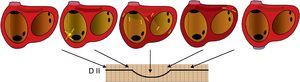

Figura 2. Representación esquemática de la secuencia de activación auricular en una taquicardia auricular focal originada en la porción inferior de la cresta terminal, en relación con la onda P en derivación II. Las flechas indican el progreso de la activación. Las líneas de base planas corresponden a periodos de ausencia de activación. D: derivación.

Figura 3. Representación esquemática de la secuencia de activación auricular en un aleteo auricular típico en relación con la onda de aleteo auricular en derivación II. En este caso no hay periodos de silencio porque la activación gira constantemente. La porción más plana de la onda de aleteo auricular corresponde a la activación del istmo cavotricuspídeo, con poca masa miocárdica D: derivación.